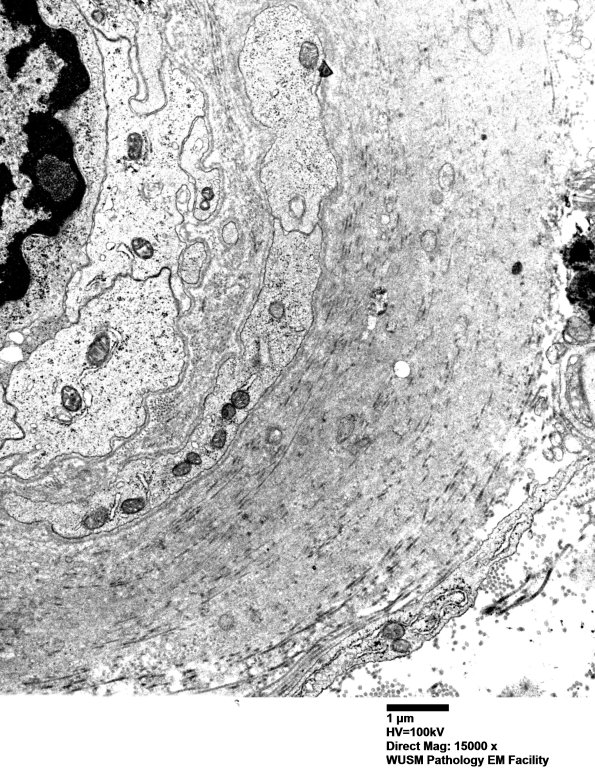

Many endoneurial blood vessels show significant mural thickening consisting largely of collagen but including some fragments of basal lamina. (electron micrograph)